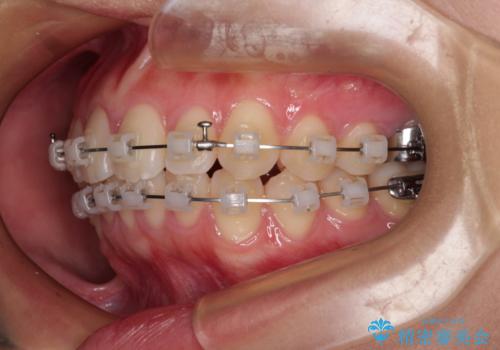

- 矯正装置

- 審美装置

- 治療期間

- 11ヶ月

- 治療回数

- 10-30回